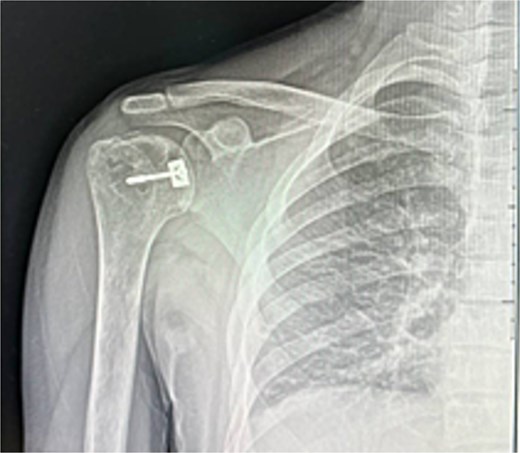

He was counseled for open reduction and modified McLaughlin procedure. Through a deltopectoral approach, open reduction was achieved, and subscapularis with lesser tuberosity was transferred to the defect and fixed with a partially threaded screw. Postoperative X-rays showed satisfactory reduction (Fig. 3). He was discharged the next day in an external rotation brace.